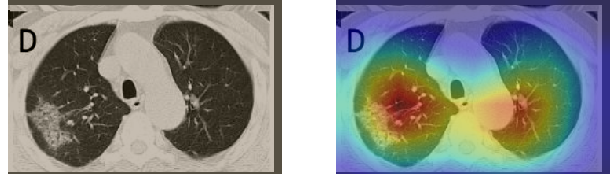

In order to make our models more transparent and provide detailed visual analysis, we present the Grad-CAM localization maps obtained by different models. We consider CT images with COVID-19 abnormalities from the test set of each dataset and highlight the important regions considered for the prediction. For the SARS-CoV-2 dataset we use the Inception V3 model. Figure 13 shows the original CT images and their localization maps. Our model is capable to detect regions that show abnormalities in the CT scans.

In a similar way, we consider classifying the test CT scans from the COVID-19 dataset by the DenseNet169 model and highlight the important regions considered for predictions. We present the original CT images and their localization maps in Figure 13. We can also see that our model is capable to detect the COVID-19 related regions as marked (small square in some images) by expert radiologists.

A wide variety of typical and atypical CT abnormalities have been reported for COVID-19 patients in various studies [58, 59]. So, we tested our models on external CT images extracted from these two publications as they feature typical findings of COVID-19 pneumonia marked by specialists. In order to make sure that not any of the extracted images are unintentionally included in our datasets, specifically the COVID19-CT dataset, we use the model trained on the SARS-CoV-2 dataset. First, the InceptionV3 model is employed to classify the extracted CT images. The model is able to correctly classify the given CT images as COVID-19. Second, in order to interpret the model’s generalization capabilities, we apply the Grad-CAM technique to visualize the regions of abnormalities that are considered. By assessing the different CT images in Figure 15, we can see that the model accurately localizes the disease-related regions. Even more interesting is the fact that the model ignores any specific marks in the images like letters and only localizes the COVID-19 related regions. These visual explanations show the success of our models to learn relevant, generic visual features related to COVID-19 and are capable to correctly classify CT images outside the datasets on which they are trained.